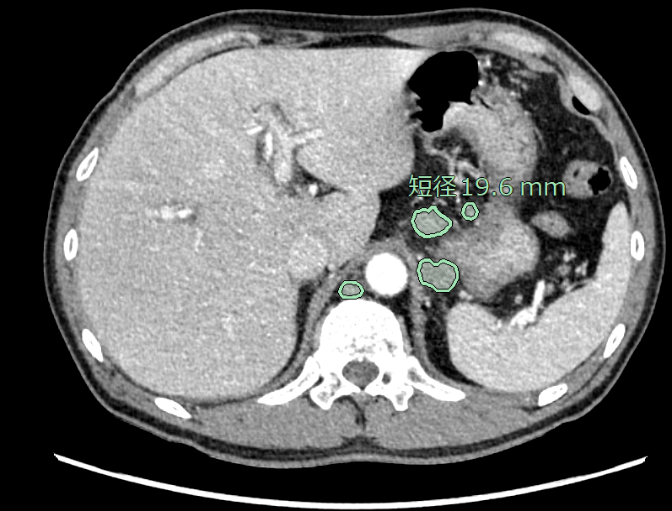

リンパ節は全身に存在しており、想定外の箇所が腫大することもあるため、読影に大きな負担がかかっています。従来、CT画像(造影・非造影)において、縦隔・腋窩リンパ節の抽出が可能でしたが、今回、頸部・腹部(大動脈周囲、骨盤部)でもリンパ節の抽出ができるように対象範囲を拡充しました。縦隔・腋窩だけではなく、頸部・腹部も含めた箇所における腫大傾向のリンパ節を拾い上げ、自動で短径計測を行います。癌の転移検索の支援に繋がることが期待されます。

腹部CT画像でのリンパ節抽出